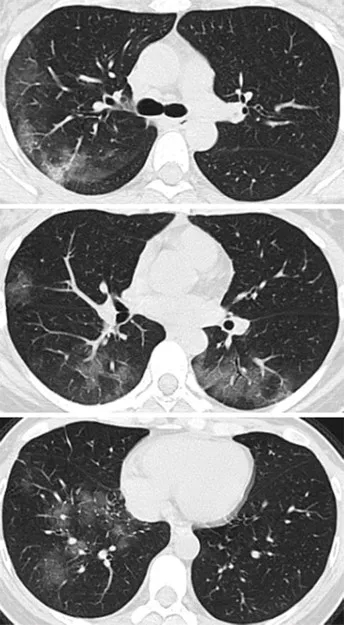

病例2,41岁女性,去了一趟武汉,

回来后,开始发热咳嗽,

4天后,她感觉呼吸困难,

去医院X线胸部拍片,检验血液,

都没有发现有啥异常。

但是CT扫描发现

两侧肺周边出现多处斑片状毛玻璃样显影。

01-3.webp

图片来自《Radiology》杂志

来自Internet图片搜索